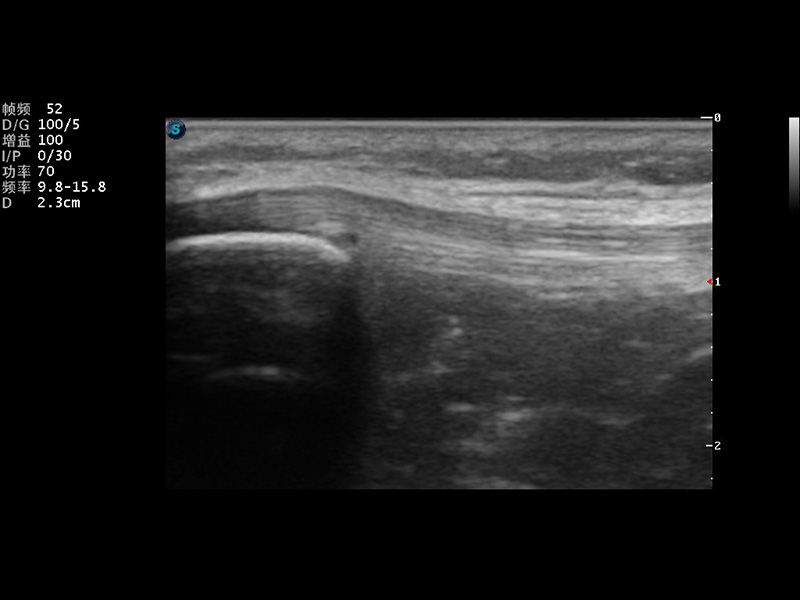

S9便携式彩色多普勒超声诊断仪是16877太阳集团研发的高端便携彩超设备,外观设计新颖、产品性能卓越。S9在便携超声领域采用了突破传统的触摸屏交互设计,并以先进的软件硬件技术和设计理念,为您带来清晰的图像质量、稳定的工作性能和便捷的操作体验。